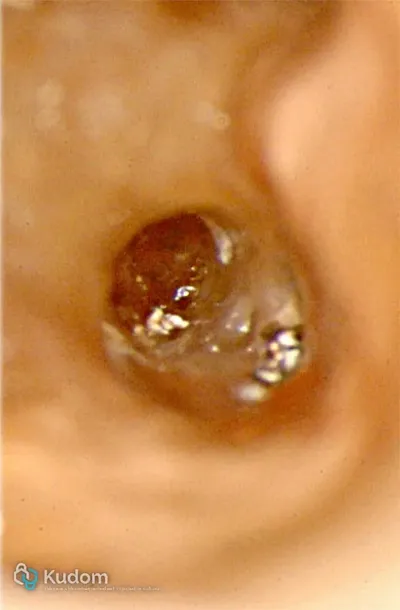

Ritrattamento di un molare inferiore con gestione di perforazione iatrogena a livello della forcazione, sotto l'imbocco radicolare.

Ritrattamento endodontico complesso di un primo molare inferiore con lesione alla forcazione e otturazione di un canale laterale con successivo build-up per overlay a ricopertura cuspidale.